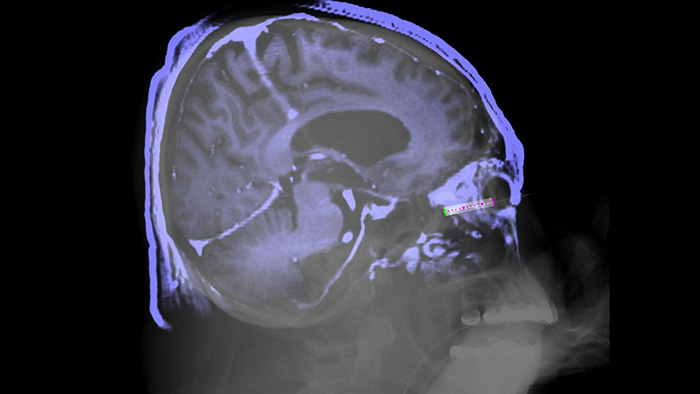

O SmartCT Soft Tissue oferece uma técnica de aquisição de TC de feixe cónico (CBCT) aumentada com orientação passo a passo. É possível aceder às ferramentas avançadas de medição e visualização 3D através do módulo de ecrã tátil junto à mesa. O utilizador é orientado através de passos-chave para adquirir imagens CBCT corretamente à primeira1 e para simplificar o seu fluxo de trabalho.